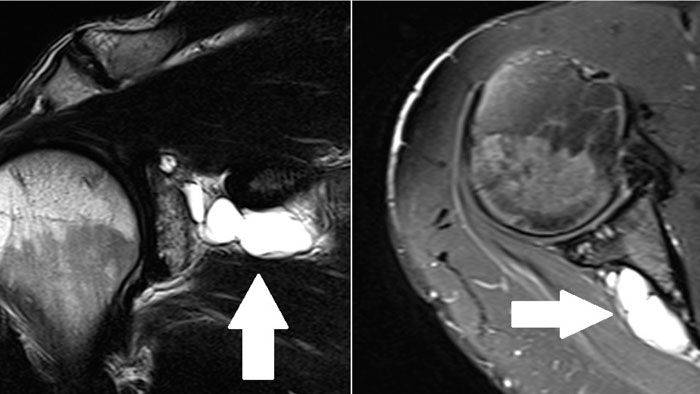

Повреждения вращательной манжеты

К повреждению сухожилий вращательной манжеты могут приводить несколько причин:

- дегенеративные изменения;

- сужение пространства между акромионом и головкой плечевой кости;

- травма;

- хроническая травматизация.

Дегенеративные изменения связаны с нарушением кровообращения сухожилий вращательной манжеты, процессом старения и износом тканей, а также с качественными изменениями коллагеновых волокон в составе сухожилий.

Сужение пространства между акромионом и головкой плечевой кости (импинджмент-синдром) возникает на фоне особого строения акромиального отростка или после получения травмы. Сухожилие надостной мышцы, проходящее в данном пространстве, попадает как бы в тиски и постепенно сдавливается.

Характерными травмами являются падение на область плечевого сустава или на вытянутую вперед руку, резкое поднятие тяжести, резкое отведение руки в сторону.

Частые микротравмы области плечевого сустава возникают у людей тяжелого физического труда и бросающих атлетов. К типичным профессиям можно отнести и тех, у кого работа связана с длительным положением руки на уровне 90и выше. Это, к примеру, парикмахеры, стоматологи, электрики, плотники, маляры.

Симптомы разрыва вращательной манжеты.

Небольшие разрывы или частичные повреждения могут проходить бессимптомно. Но чаще всего ведущим признаком является боль. При факте травмы боль возникает резко, а при повторяющихся нагрузках она усиливается постепенно и со временем нарастает. Наибольшая интенсивность боли определяется при отведении руки по дуге от 60 до 120. Периодически боль усиливается ночью и приводит к нарушению сна.

Во время осмотра можно выявить снижение силы мышц травмированной конечности. Болевые ощущения ограничивают объем движений в плечевом суставе и приводят к развитию контрактуры (тугоподвижности).